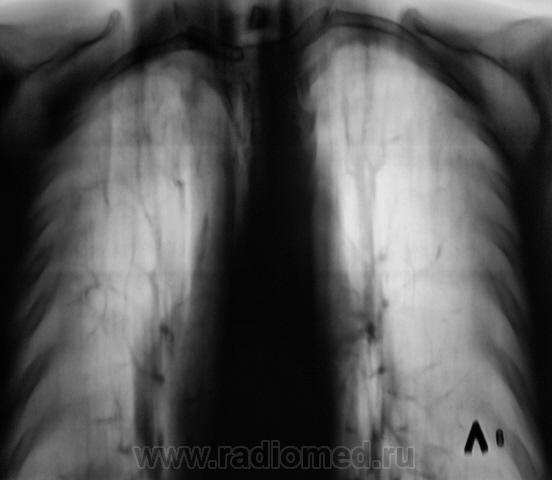

Прямая дорога к фтизиатру. Неясно, что творится в средней доле, создается впечатление инфильтрации и наличия полости. Желательны ТГ ср. доли или хотя-бы прицельный снимок. Да и на правой верхушке поставить однозначно "остатачные явления" я бы не рискнул.

Да складывается впечатление о течении спецпроцесса. А в средней доли или инфильтрация или грудная мышца с соском. Но каков прицел!!! Заметить такую тенюху на верхушке а потом еще и раскрутить! Кстати Валентин Львович, а как на счет рентген нагрузки, как Вы полагаете сколько можно сделать томограмм, а то меня зав. третирует, что я выполняю по 5-6 томограм, причем они меньше Ваших максимум 24х30.

А справа на верхушке то не туберкулома?

да, туберкулома